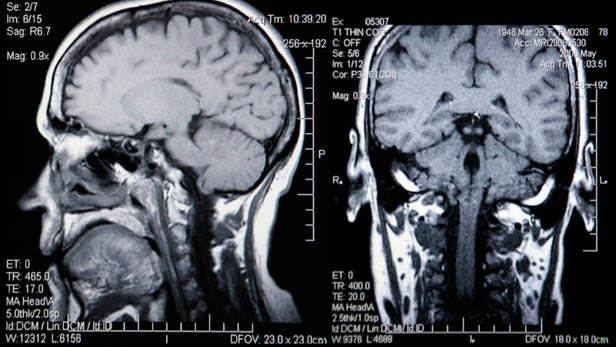

محققان دانشگاه انگلیسی موفق شدند با استفاده از اسکن‌های ام.آر.آی و الگوریتم‌های یادگیرنده سن بیولوژیک را محاسبه کنند.

حال محققان دانشگاه انگلیسی موفق شدند با استفاده از اسکن‌های ام.آر.آی و الگوریتم‌های یادگیرنده سن بیولوژیک را محاسبه کنند. روشی که در صورت تایید می‌تواند کار را بسیار ساده‌تر و سریع‌تر کند. این روش در اصل از سال 2010 آغاز شده و در طی این سال‌ها تکمیل و به روز شده است. الگوریتم‌ مورد استفاده در این تحقیق، با استفاده از بررسی غشای مغز می‌تواند میزان کلی از دست رفتن ماده سفید و خاکستری مغز را که با بالارفتن سن افزایش می‌یابد، پیش‌بینی کند.

با توجه به گزارش منتشر شده از تیم تحقیقاتی چالش موجود در این تحقیق، ایجاد یک استاندارد برای اندازه‌گیری کاهش حجم غشای مغز در ام.آر.آی بوده است. برای این کار مغز بیش از دو هزار فرد سالم اسکن شده تا محققان بتوانند با انجام مقایسه بین این تصاویر و داده‌های موجود، نرخ تحلیل رفتن مغز را محاسبه کنند.

برای تایید نتایج این تحقیق، دانشمندان  از تصاویر مغز افرادی که در 73 سالگی از مغز آنها اسکن گرفته شده‌ بود استفاده کردند. محققان به این موضوع پی بردند که مغز بیمارانی که میزان تحلیل رفتن ماده سفید و خاکستری آنها بیشتر باشد پیرتر از سن بیولوژیک خواهد بود و به همین دلیل آنها در ظاهر مسن‌تر بوده و توانایی‌های کمتری نسبت به دیگر همسالان خود دارند.‌ به علاوه در صورتی که سن مغز از سن تقویمی افراد بیشتر باشد، فرد به احتمال زیاد تا پیش از رسیدن به 80 سالگی جان خود را از دست خواهد داد.